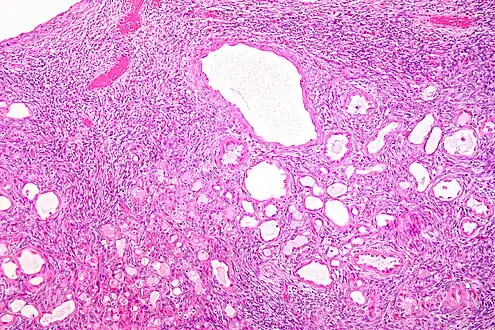

| Micrograph of a cystic nephroma (left of image). Normal kidney is seen on the right. H&E stain. | |

Cystic nephroma: Microscopic appearance.

Micrograph of a cystic nephroma. H&E stain.

The characteristics of cystic nephromas are:

- Cysts lined by a simple epithelium with a hobnail morphology, i.e. the nuclei of the cyst lining epithelium bulges into the lumen of the cysts,

- Ovarian-like stroma that has a:

- Spindle cell morphology, and has a

- Basophilic cytoplasm.